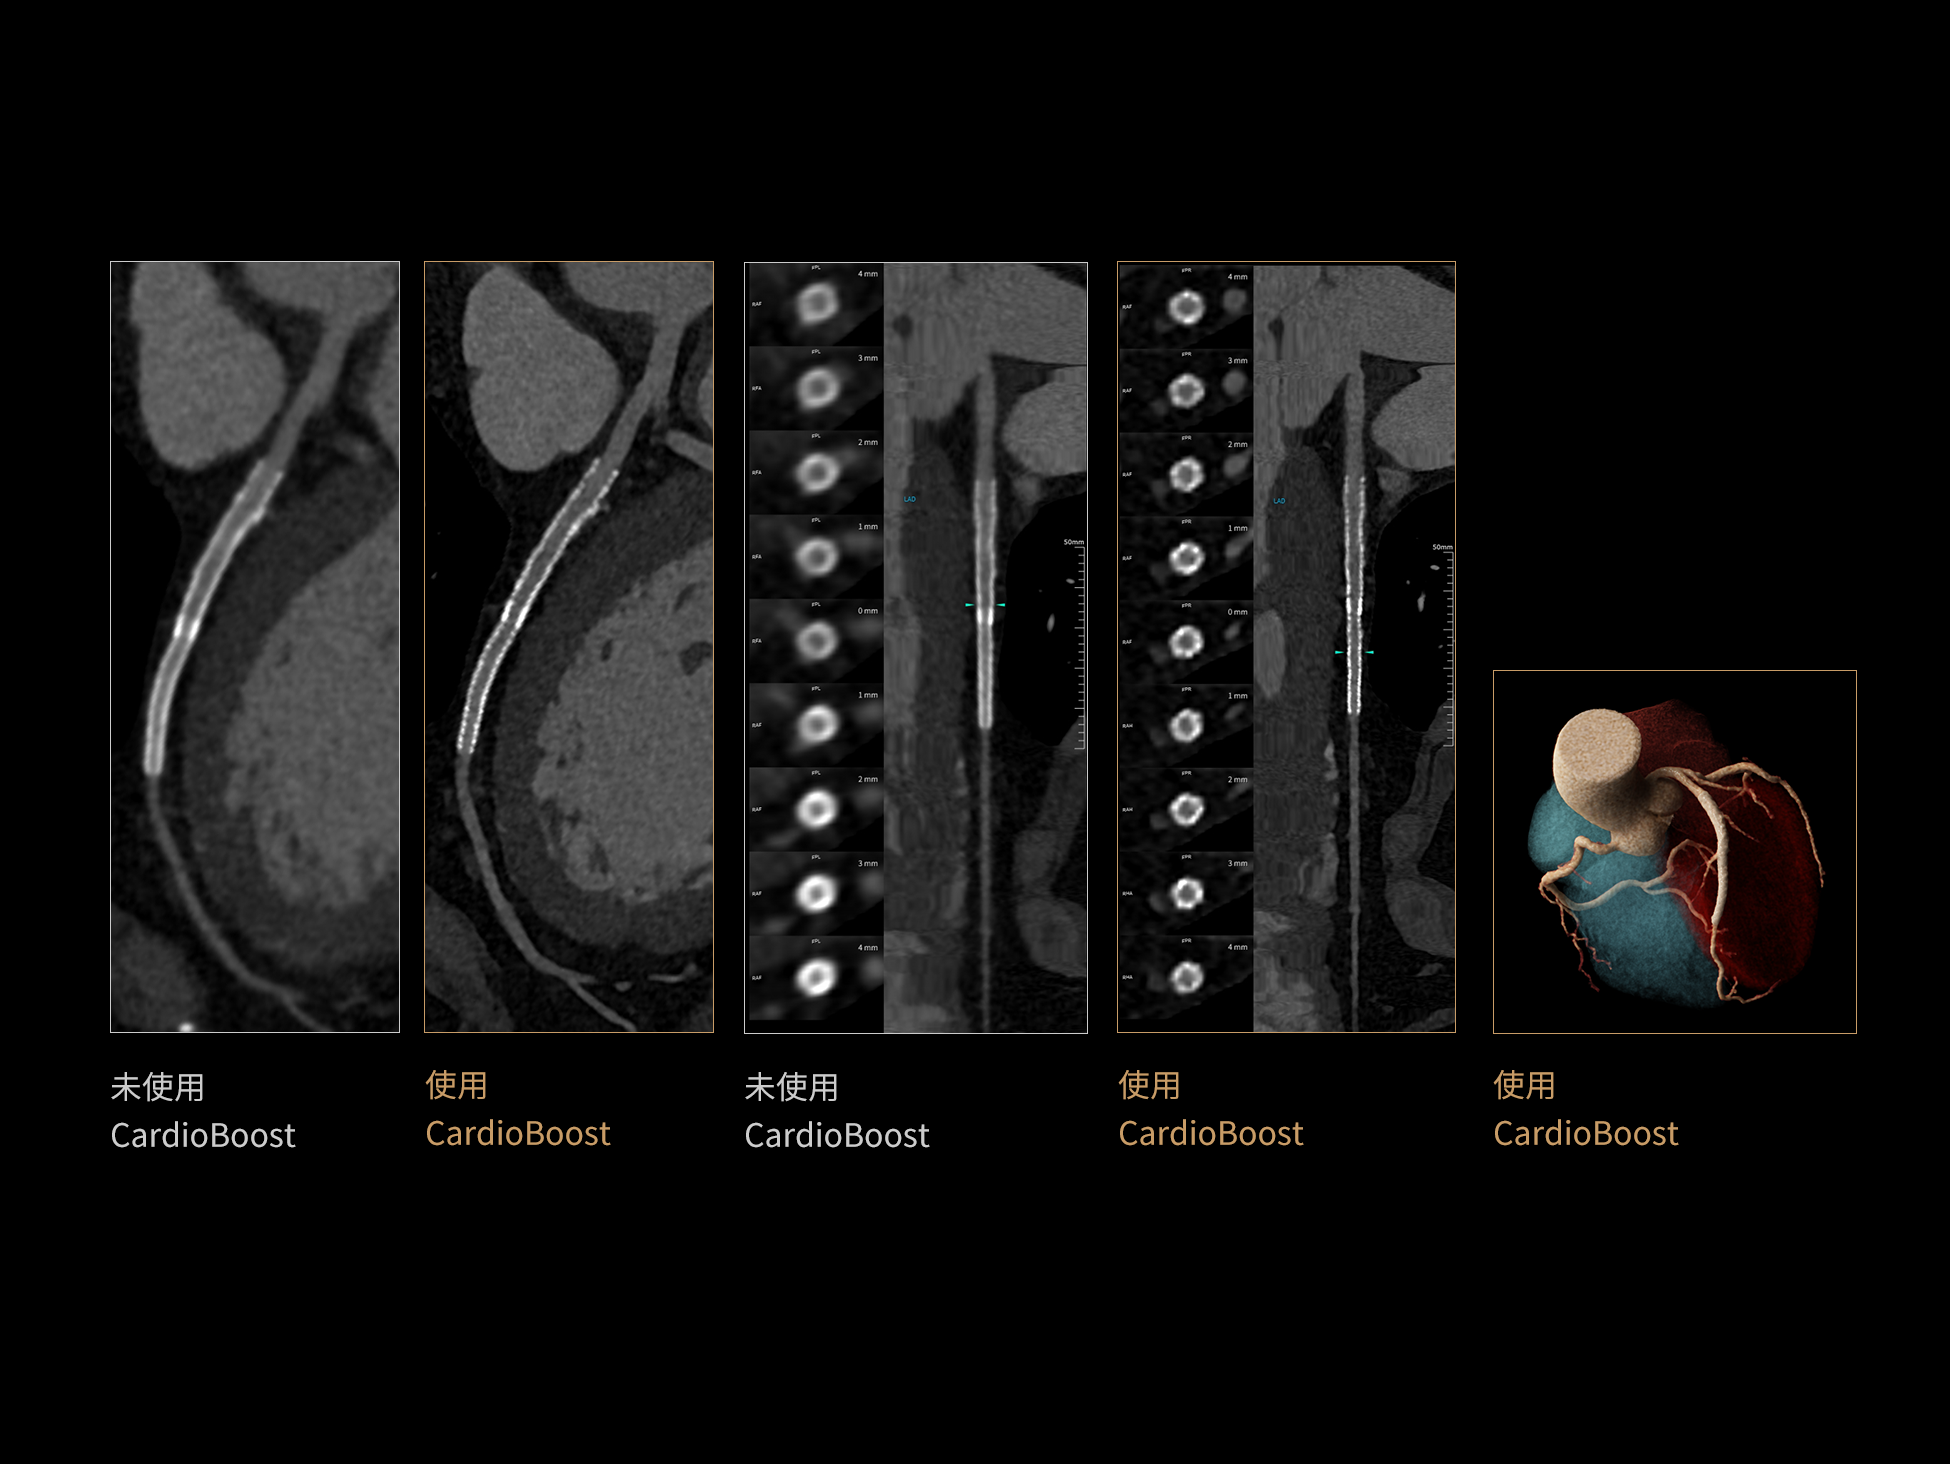

CardioBoost:专属网络设计,重塑心脏影像表现

uCT 868 搭载联影最新一代 uSense 人工智能平台,将智能化深度融入 CT 扫描全流程,从感知细微生理运动到精细结构探测,再到多场景诊疗优化。以 AI 为核心驱动力,uSense 重塑成像各环节,打造高效、高清的智慧扫查体验。在心脏成像领域,uSense 结合宽体探测器、心脏专研AI重建算法与AI冠脉运动追焦技术,在保持低剂量的同时,有效抑制运动伪影,精准呈现软斑块、混合型斑块及支架细节,助力冠脉成像惠及更多患者。针对多科室疾病临床应用场景,uSense 平台提供全方位的智能解决方案:包括头部运动伪影智能校正、金属植入物伪影抑制、扫描视野扩展等先进算法。这些创新技术使 uCT 868 能够构建覆盖全场景的智能诊疗体系,持续拓展 AI 赋能医学影像的边界。